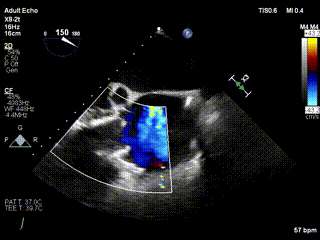

三例患者入院后,葛均波院士團隊周達新教授、潘文志教授、張源博士、陳莎莎博士及心超室的潘翠珍教授、李偉教授對患者的情況進行詳細評估和討論,最終決定為三例患者選擇LuX-Valve Plus40mm、50mm和50mm型號的瓣膜進行手術治療。手術后即刻拔除氣管插管,術后患者三尖瓣反流癥狀得到顯著改善,復查心超結果顯示人工三尖瓣瓣膜支架固定穩定,瓣葉關閉形態未見異常,未見明顯反流。